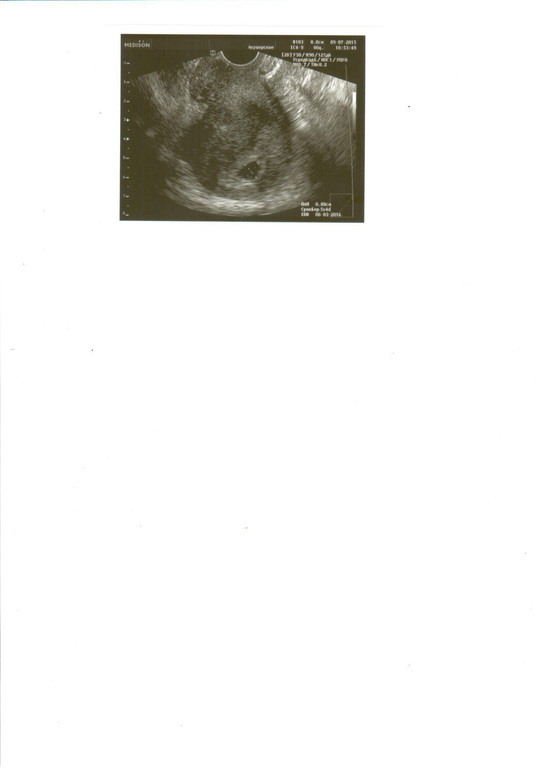

девочки от месячных у меня сейчас 5 недель и два дня ПЯ соответсвуетисроку 4-5 недель эмбрион и желточный мешочек пока не видно есть еще отслойка плодного яйца эндометрий 21 желтое тело 11. Девочуи у кого на 5 недели не видели эмбрилн и желточный мешочек чем все закончилось. А то я очень преживаю. Всем заранее спасибо.

5 недель не видно эмбрион и желточный мешочек

Всем привет! У меня ситуация, наверное, хуже всех! На 5 недели беременности мне сделали узи было все идеально-плодное яйцо, желточный мешок, эмбрион ещё не визуализировался, через несколько дней мне стало плохо, были коричневые выделения, пошла на узи-у меня отслойка, желточного мешочка нет, эмбриона по прежнему нет, сдала хгч-оно растёт, иду опять на узи, срок 5 недель и 5 дней-плодное яйцо выросло, отслойка также есть, эмбриона также нет, желточный мешочка также нет, врач настаивает на фармаборте, это моя первая беременность, не получалось долго, врачи ставили бесплодие и тут такое чудо и я должна его убить, собственноручно выпить эту таблетку для фармаборта…я обратилась к другому врачу, та уложила меня дома на сохранение назначила дюфастон и фолибер пить, и на сроке 7 недель прийти на узи, послушала ее, лежу дома не встаю, она сказала эмбриона не видно потому что он крошечный, но, я думаю, куда тогда делся желточный мешок? Девочки, может у кого-то что-то похожее было, поделитесь, пожалуйста🙏🏻

А желточный мешочек видно было. Знаю что рано. Хотела себя успокоить а получилось с точностью наоборот.

Всем огромное спасибо просто на узи узистка так это сказала что типа он должен быть а его нету я за мешочек.

Девочки всем огромное спасибо вы меня успокоили. А через неделю пойду на узи посмотреть что с отслойкой.